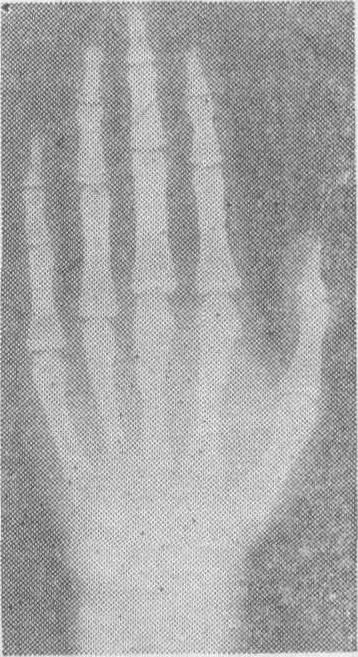

袁×× 女 14.4岁摄片前2月月经来潮,骨龄13.5岁

14岁初潮女生X线骨龄片(据北京医学院儿少卫生教研室,1981)